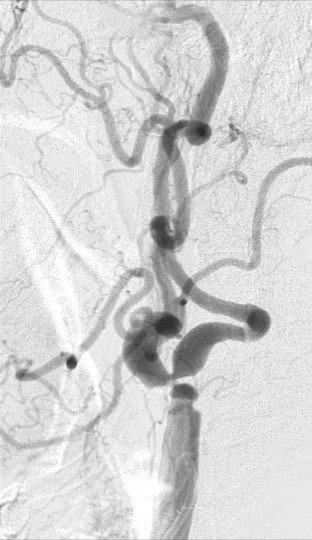

Resim: Karotis darlığında stent uygulaması

Stent için uygun olmayan cerrahi tedavi gerektiren hastalar

1. Ana karotis arter çıkışında büklümlü olması

2. İnternal karotis çıkışında 90 derecelik açılanma

3. Hem İnternal, hem de eksternal karotis’de ciddi darlık

4. İnternal karotisin sağa açılı çıkışı

5. Ana ve İnternal/Eksternal karotis stenozu

6. İnternal karotiste ‘de 3 loop

7. Yoğun kalsifikasyon

8. Dolma defekti